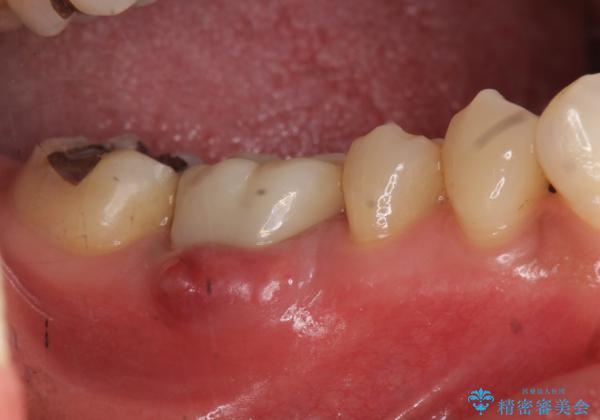

初診時には歯肉が腫れており、膿が出ている状態でした。

被せ物を外したところ、歯が大変薄くなって割れており、残念ながら残すことはできないと説明しました。

初めての根の治療には見えないくらい、かなり歯が削ってあり、薄くなっていて割れても仕方ない状態でした。前の状態を見ていないので何とも言い難いですが、他の歯に比べこの歯だけ極端に状態が悪かったです。

当院は最後まで歯を残せるように、きちんと破折していないかチェックし、患者様に写真を確認していただいたうえで抜歯をするかを相談していきます。